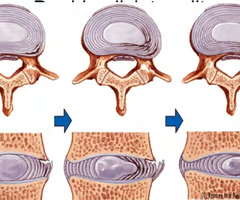

Intervertebral disc (cushion-like pad made of 2 parts)

Nucleus pulposus

Inner gelatinous material that acts like a rubber ball to give disc elasticity and compressibility

Annulus fibrosus

Strong collar surrounding nucleus pulposus; made of fibrocartilage and collagen fibus.

Herniated (slipped) disc

Occurs when spongy nucleus pulposus protruded thru a rupture in annulus fibrosus and presses on the spinal cord or spinal nerves.

Nucleus pulposus

Annulus fibrosus

Herniated (slipped) disc